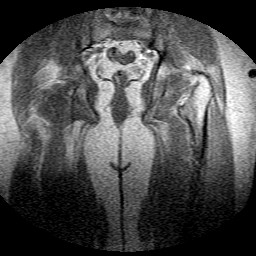

Esami: RMN BACINO

Evidenti e simmetriche alterazioni osteofitosiche in regione coxo femorale con riduzione delle rime articolari. Degenerazione completa del cercine glenoideo. Non attuali segni di versamento articolare. Non segni di edema osseo che escludono attuale algodistrofia od osteonecrosi. Lieve e simmetrica riduzione del trofismo della muscolatura glutea.